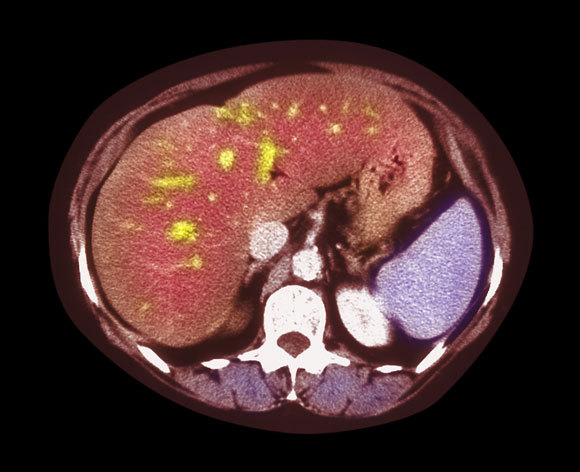

מחלת הכבד השומני נחשבת כיום מגפה של ממש. צילום CT של כבד שומני, בו ניתן לראות שהכבד מוגדל, ויש בו הצטברות שומן (כתמים צהובים) | Simon Fraser, Freeman Hospital, Newcastle Upon Tyne, SPL